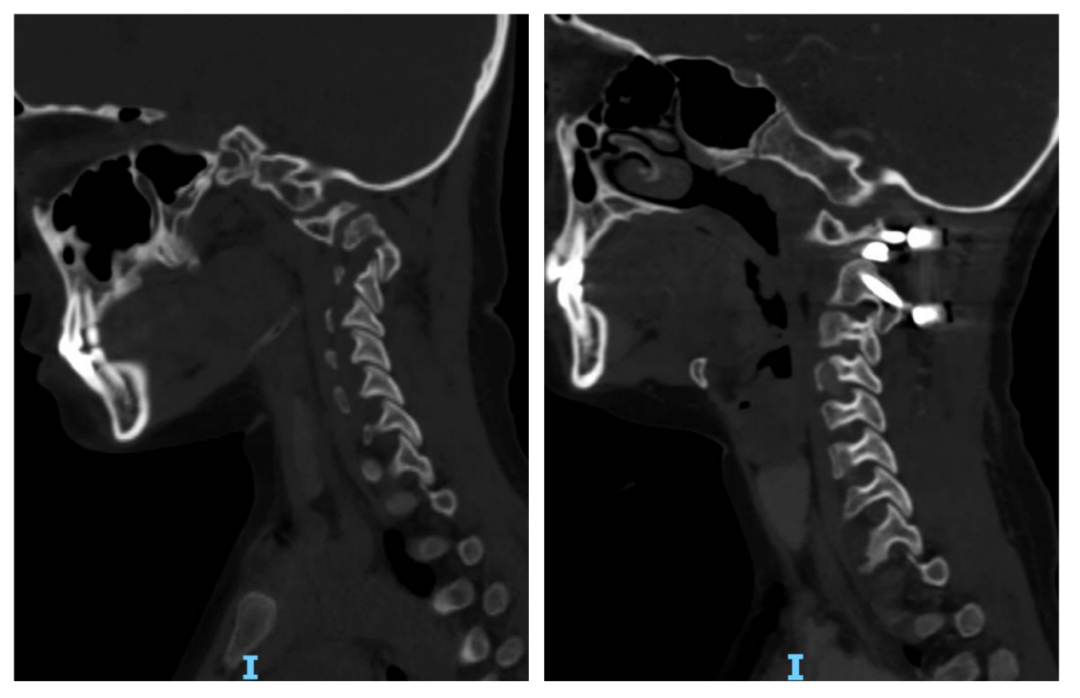

*术前:寰枢椎脱位畸形;术后:寰枢椎椎体间融合,颈椎生理曲度恢复。

寰枢椎脱位是脊柱外科领域极具挑战性的疾病,其手术治疗风险极高。后路关节间松解复位内固定手术需在延髓、颈髓交界区这一“生命禁区”操作,稍有不慎便可能损伤椎动脉或脊髓,导致瘫痪甚至危及生命。而关节间融合技术则是手术成功的关键——通过精准处理寰枢关节间隙,实现解剖复位与即刻稳定,不仅能有效解除神经压迫,更能显著降低术后远期融合失败、内固定松动等并发症风险,为患者长期生活质量提供保障。此外,首都医科大学宣武医院神经脊柱中心主导制定的《后路寰枢椎关节间撑开复位融合技术治疗寰枢椎脱位专家共识2024》,已经成为治疗寰枢椎脱位的临床指南。宣武医院济南医院作为共识制定单位之一,进一步体现出中心在学术领域的权威地位。本次会议期间的两台手术在显微镜下完成高难度操作,患者术后恢复良好,已顺利出院。